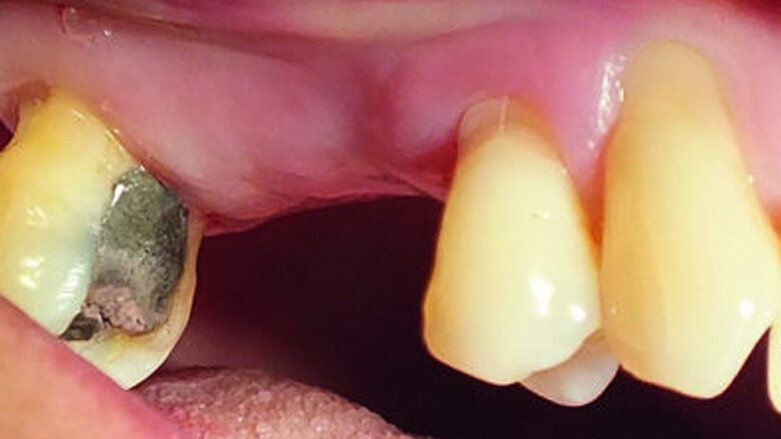

A 52-year-old female patient was concerned about the appearance of her smile. Her upper right first molar and second premolar had been missing for several years (Figs. 1 and 2). She was otherwise a fit and healthy non-smoker.

Fig. 1: The patient’s upper right first molar and second premolar had been missing for several years.